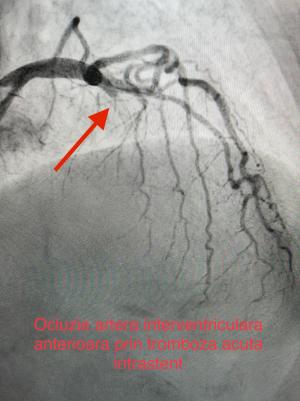

O intervenție medicală de urgență pentru salvarea unei paciente care suferise un stop cardiac a avut loc la Spitalul de Urgență Galați. Pacienta a fost resuscitată, iar imediat echipa medicală…